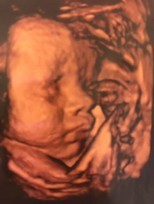

ซาวด์ตอน15+5wค่ะ ตอนนี้19w แล้ว ลูกสาวจ้า